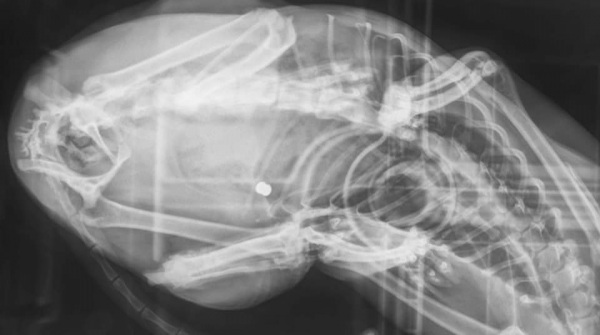

"Witam wszystkich posiadaczy i nie posiadaczy zwierzęcych przyjaciół. Pisze, aby ostrzec Was przed człowiekiem, który z przyczyn, których pojąć nie potrafię, strzela do bezbronnych zwierząt. Wczoraj tj. 27.04, zauważyłam, że moja kotka dziwnie się zachowuje, wygląda jakoś "nieswojo", widać było po niej również, że chodzenie jak i siedzenie sprawia jej trudność oraz ból. Na ciele znalazłam ranę, początkowo przypuszczałam, że to efekt walk terytorialnych z innymi kotami, atak jakiegoś psa lub niefortunne zahaczenie się jej o coś, przykładowo siatkę ogrodzeniową. Po wizycie u lekarza weterynarii, który stwierdził, że rana jest dokładnie jak po postrzale z.......WIATRÓWKI (!!!), zdjęcia RTG tylko to potwierdziły.